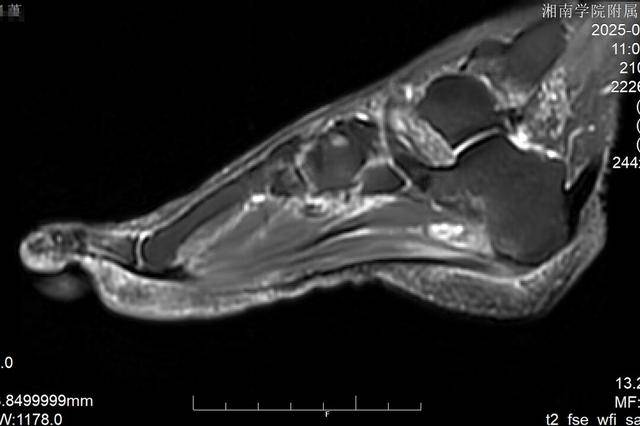

接诊后,李杨主任医师迅速带领团队为陈阿姨展开全面检查。结合患者的症状表现、病史资料以及影像学检查结果,团队明确诊断:陈阿姨患上的是足底筋膜炎,且已出现筋膜粘连与赘骨增生情况。由于病情迁延较久,传统治疗手段已难以达到理想效果,手术干预成为必要选择。考虑到陈阿姨年事已高,且希望能尽快恢复正常生活,团队经过反复研讨,最终决定采用关节镜微创技术,为其实施足底筋膜松解术与病灶清除术。

手术过程中,医疗团队仅在患者跟骨内侧切开两个0.5厘米的微小切口,通过关节镜清晰观察到病灶内部情况,精准完成粘连足底筋膜的松解操作,同时磨除了增生的囊肿组织。整个手术出血量极少,创伤小,术后陈阿姨当即感觉足跟疼痛明显减轻。